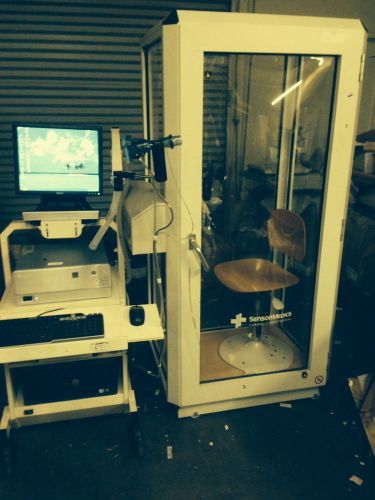

VIASYS VMAX ENCORE 22 PULMONARY FUNCTION TEST SYSTEM WITH AUTO BOX